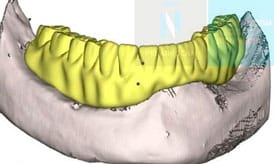

Se diseñan y fabrican a medida mediante tecnología digital (CBCT, CAD/CAM, sinterización láser), lo que permite un ajuste preciso a la superficie del hueso maxilar y a la anatomía del paciente.

Antes de la cirugía se realiza un estudio individualizado de cada paciente mediante pruebas de imagen avanzadas como la tomografía computarizada (CBCT) y escaneados intraorales. Gracias a la mejora del diseño y la fabricación digital asistida por ordenador, podemos conocer al detalle la anatomía ósea y diseñar un plan de tratamiento personalizado para la colocación del implante yuxtaoseo.

3. Diseño personalizado del implante

Con la información obtenida del estudio, el equipo diseña de forma digital los implantes a medida y se planifica su posición sobre la pantalla del ordenador. A partir de este diseño, se fabrican unas férulas quirúrgicas que guiarán la colocación del implante subperióstico durante la cirugía, asegurando que la estructura se adapte perfectamente al hueso del paciente.

En este caso mostramos el antes y el después de un paciente con atrofia ósea severa y la rehabilitación conseguida gracias al tratamiento de implantes subperiósticos en Valencia:

Antes

Proceso

Después